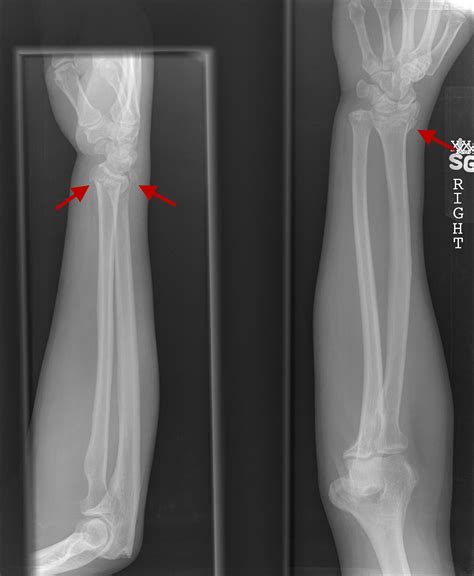

Diagnosing an Ulnar Styloid Fracture

Diagnosing an ulnar styloid fracture typically involves a combination of physical examination and imaging tests. The diagnostic process may include:

• X-rays: These are the primary imaging tool used to confirm the diagnosis. X-rays can show the location and extent of the fracture.

• Non-Union: The bone fragments do not heal properly, leading to a persistent fracture.

• Malunion: The bone heals in a misaligned position, which can affect wrist function.